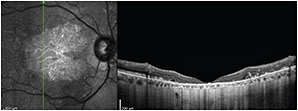

Following intravitreal bevacizumab (Avastin, Genentech) injection, choroidal thickness returned to the level of the unaffected contralateral eye (Figure 2).16

Figure 2. Branch RVO with macular edema. A 73-year-old woman with a past medical history of hypertension who presented seven years earlier with decreased VA of 20/80 in the right eye and underwent panretinal photocoagulation and three intravitreal injections of bevacizumab. She later developed a macula-off retinal detachment and underwent pars plana vitrectomy, subretinal fluid drainage, endolaser, and C3F8 injection. The patient subsequently developed a superior vein occlusion with macular edema in the left eye three years ago; her vision decreased to 20/200, and she received three injections of intravitreal bevacizumab and one of intravitreal triamcinolone. Note the generalized thinning of the choroid in both eyes.